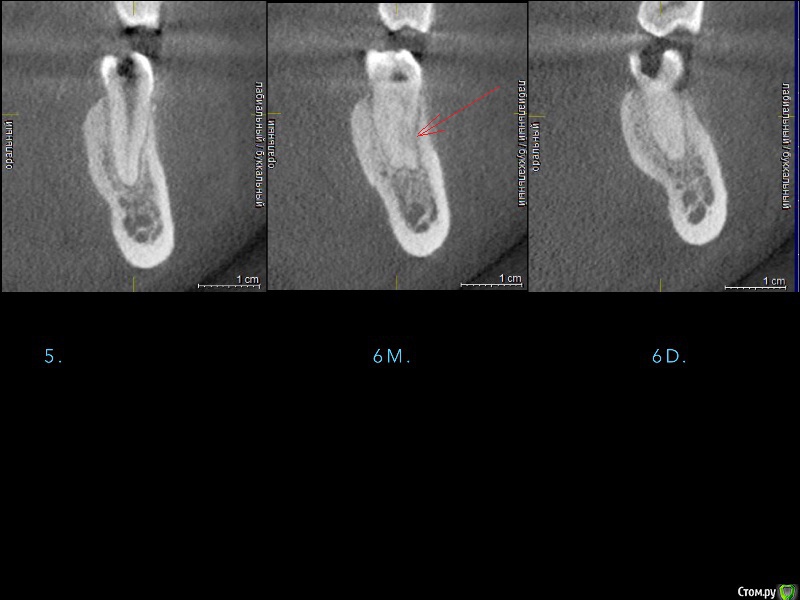

red_butler Опубликовано 9 марта, 2016 Поделиться Опубликовано 9 марта, 2016 в пятерке оба канала обработаны? 1 Ссылка на комментарий

AlexanderGudkov Опубликовано 9 марта, 2016 Автор Поделиться Опубликовано 9 марта, 2016 в пятерке оба канала обработаны?тут 1 канал всегоВ 6 обработали все 4, не помогло Ссылка на комментарий

carloss Опубликовано 9 марта, 2016 Поделиться Опубликовано 9 марта, 2016 Карен, ты же умный! Скажи что-нибудь!Если судить по тому, что из принятых тут "умных" я единственный, кто не проводит курсов, то я себя таковым не считаю)) По теме - сложно сказать.. но не в каналах дело точно - вероятность того, что два рядом стоящих зуба одновременно так атипично среагировали близка к нулю.. да нормально там вроде все.. но решение по эндо принимались бы клинически. Заметно расширение периодонта на 5 и 6.. возможно это после орто так, а может из-за воспаления.. в любом случае похоже на острый "паро" процесс наверное как пишет Астронавт вследствие неспецефического микроба.. и, возможно, широкая щель послужила "широкими входными воротами" для микроба.. Я бы сразу начал с мощных доз антибиотиков(кстати всегда при воспалениях начинаю с комбинации амоксиклав+метронидазол, я думал все так), может через пару -тройку дней сменил бы. Правда под эту теорию не очень ложится то, что было уже с другой стороны раньше, но думается первичен именно микроб, остальное способствующие факторы. Еще не очень понравилось что-то на КТ, под пятеркой.. но наверное или ментальное или артефакт, думаю топикстартер разобрался бы, если что. но не факт, что не поступил бы как тут.. 5 Ссылка на комментарий